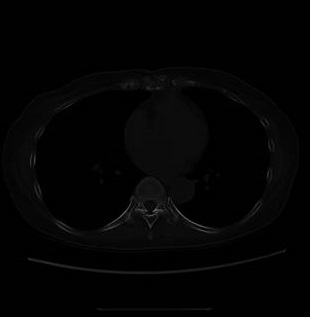

筆者がこれまで遭遇した症例には、肺転移が先に見つかり、全身の原発巣を調べた結果、甲状腺微小乳頭癌にたどり着いたものが数例あります(浸潤型微小乳頭癌)。

また、頚部リンパ節転移が見当たらないのに肺転移する事があります(信州医誌,59(2):89~95,2011)(日呼吸会誌 46(7):578-582,2008.)(Thyroid. 2009 Mar;19(3):309-11.)。

肺CTで肺転移の有無を定期的に確認する必要があると筆者は考えております。

甲状腺微小乳頭癌の中には、転移しやすい浸潤型微小乳頭癌が確かに存在します。転移しやすい甲状腺微小乳頭癌か否かを調べるのは現時点では不可能です。よって、長崎甲状腺クリニック(大阪)では甲状腺微小乳頭癌が見つかれば、肺・上半身骨CT、何らかの脳神経症状がある場合のみ脳MRIをお勧めしています。